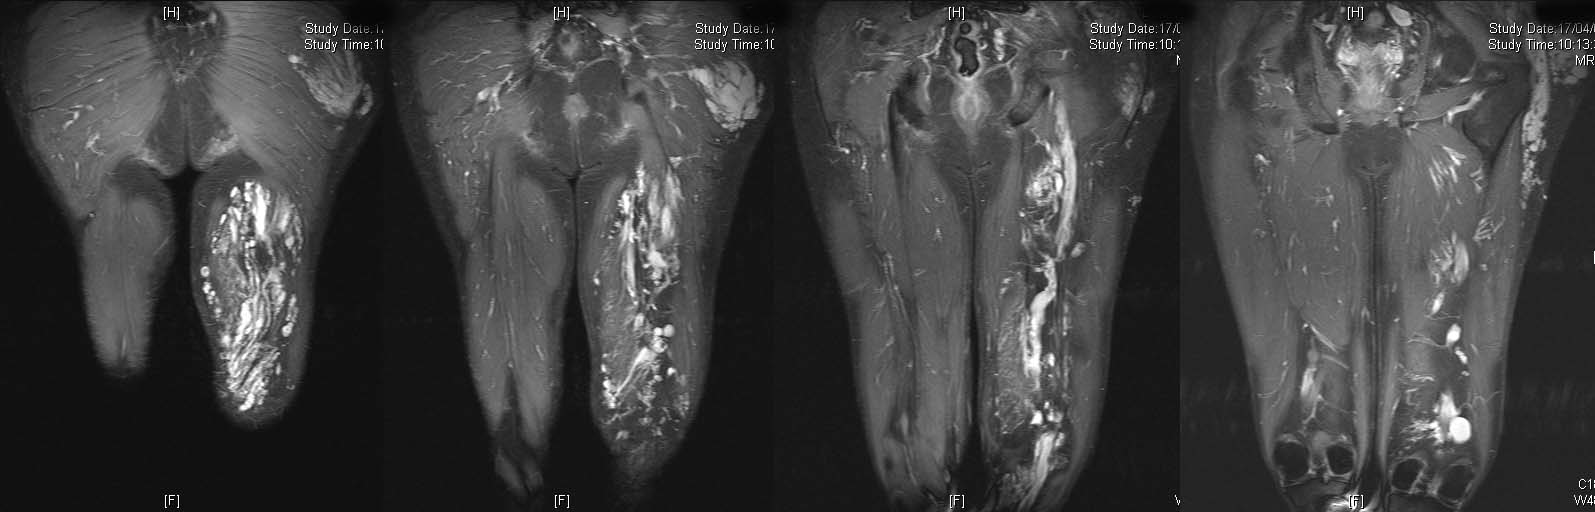

Aneurysmal bone cyst metatarsal. Benign looking expansion of the distal end of the second metatarsal. The lesion is cystic with fluid-fluid levels evident on the STIR image.

16-year-old girl complaing of pain and swelling of the foot.